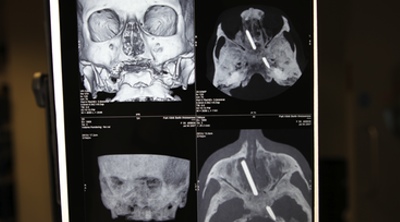

DKISS entra en el sorprendente mundo de los hospitales con 'Urgencias Bizarras' y 'Urgencias punzantes'

La cadena temática apuesta en la noche de Reyes por dos nuevos formatos centrados en ...